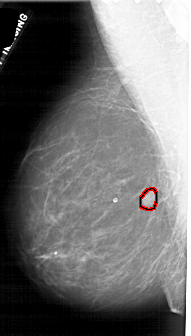

A_1880_1.LEFT_MLO

LEFT_MLO LINES 4696 PIXELS_PER_LINE 2671 BITS_PER_PIXEL 12 RESOLUTION 43.5 OVERLAY

FILE: A_1880_1.LEFT_MLO.OVERLAY

TOTAL_ABNORMALITIES 1

ABNORMALITY 1

LESION_TYPE MASS SHAPE LOBULATED MARGINS OBSCURED

ASSESSMENT 4

SUBTLETY 5

PATHOLOGY BENIGN

TOTAL_OUTLINES 1

BOUNDARY